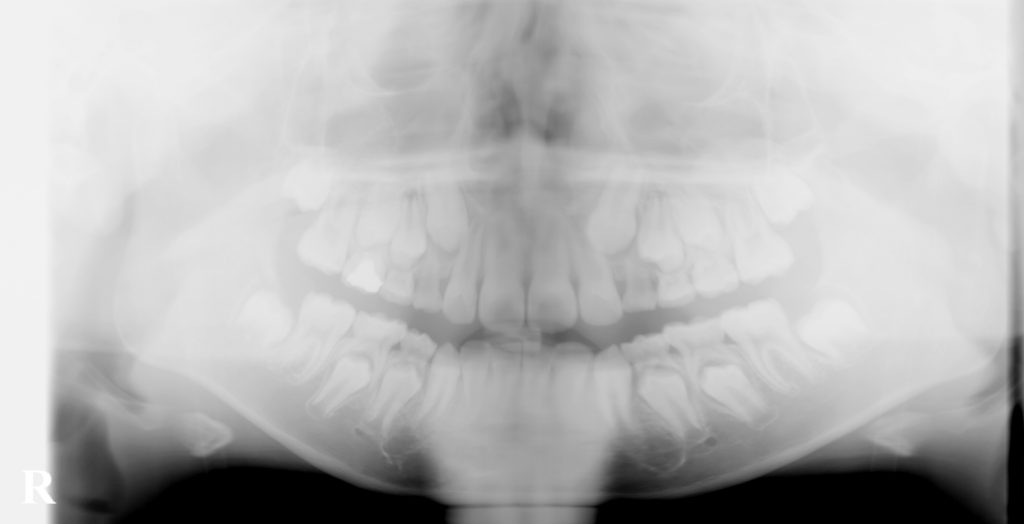

こむら小児歯科・矯正歯科で経過観察してきたケースです。

上の犬歯の位置が悪かったのですが、最終的には問題なく生えてきました。

どんなケースでも矯正治療が必要というわけではなく、正しい診断の元に経過観察することも大切です。

埋まっている上の犬歯を引っ張らなくても このようにきれいに生えてくる事もあります。